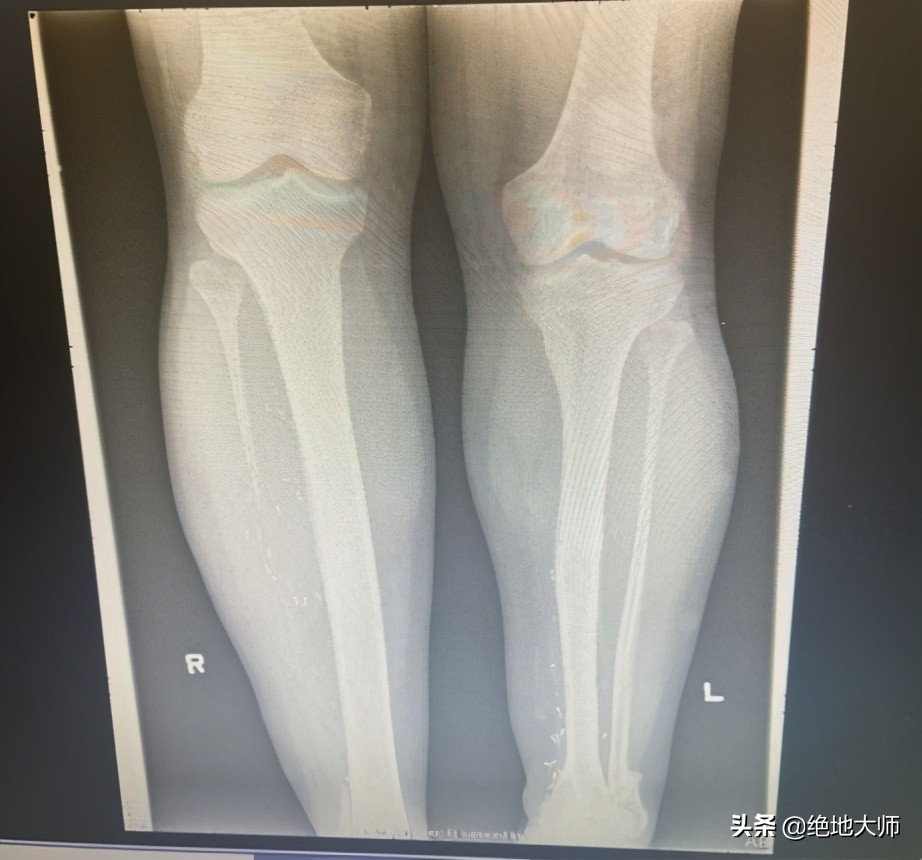

4. Structural LLD 结构性腿长不等

右侧腓骨缺失,左侧应力性骨折。

6. Structural LLD causes DJD, fracture 结构性LLD导致退行性关节病变、骨折